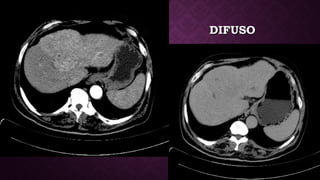

DIFUSODIFUSO

TOMOGRAFÍATOMOGRAFÍA • Por logeneral, la masa capta contraste intensamente durante la fase arterial tardía (~ 35 segundos) y luego se elimina rápidamente, llegando a ser indistinta o hipoatenuante en la fase venosa portal, en comparación con el resto del hígado. • Además, pueden estar asociados con una anomalía de perfusión en forma de cuña debido a shunts arterioportales, y esto, a su vez, puede resultar en un cambio graso focal en el hígado normal.  • También puede observarse un halo graso focal alrededor de un HCC en un hígado graso. • El trombo tumoral de la vena portal puede distinguirse de un trombo blando al demostrar mejoras.